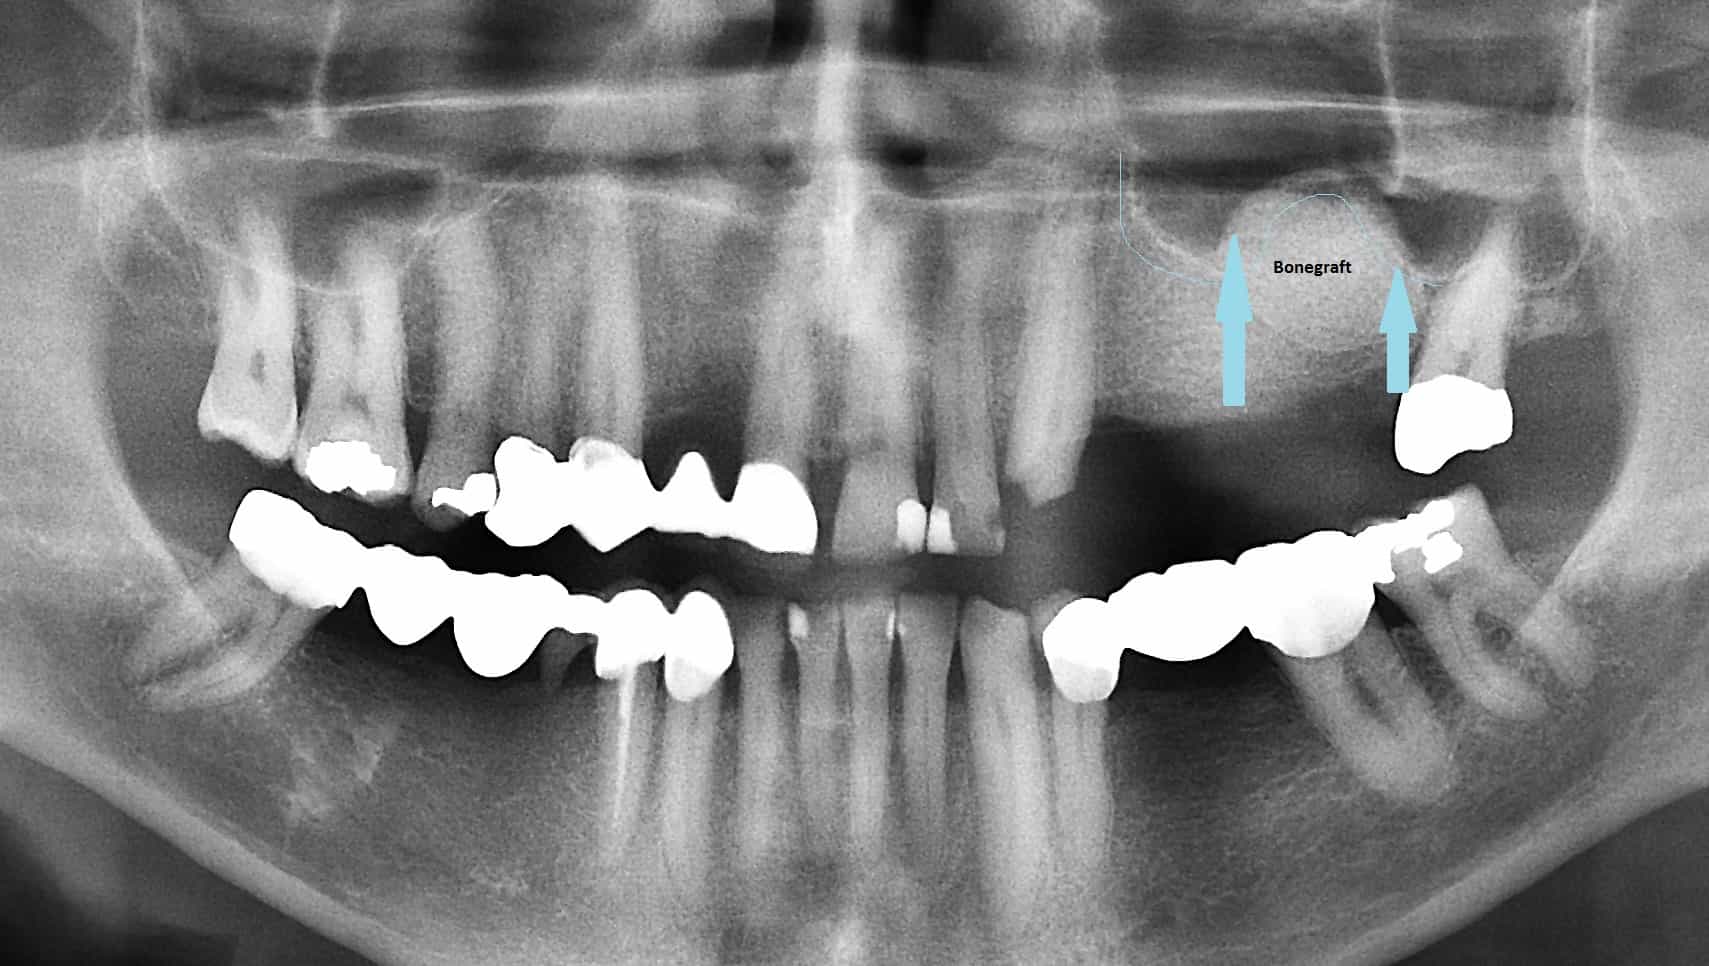

From www.facialart.com

Bone Grafting and Repair of Sinus Perforation Following Tooth Sinus Pain After Dental Crown You might experience some discomfort after having a crown placed, but after a few weeks, it shouldn’t hurt. Learn about the relationship between dental pain and sinus infections, including their causes, symptoms, and. Learn about all the possible causes of dental crown tooth. However, following a few simple steps can relieve minor sinus problems, such as discharge and reduced breathing.. Sinus Pain After Dental Crown.